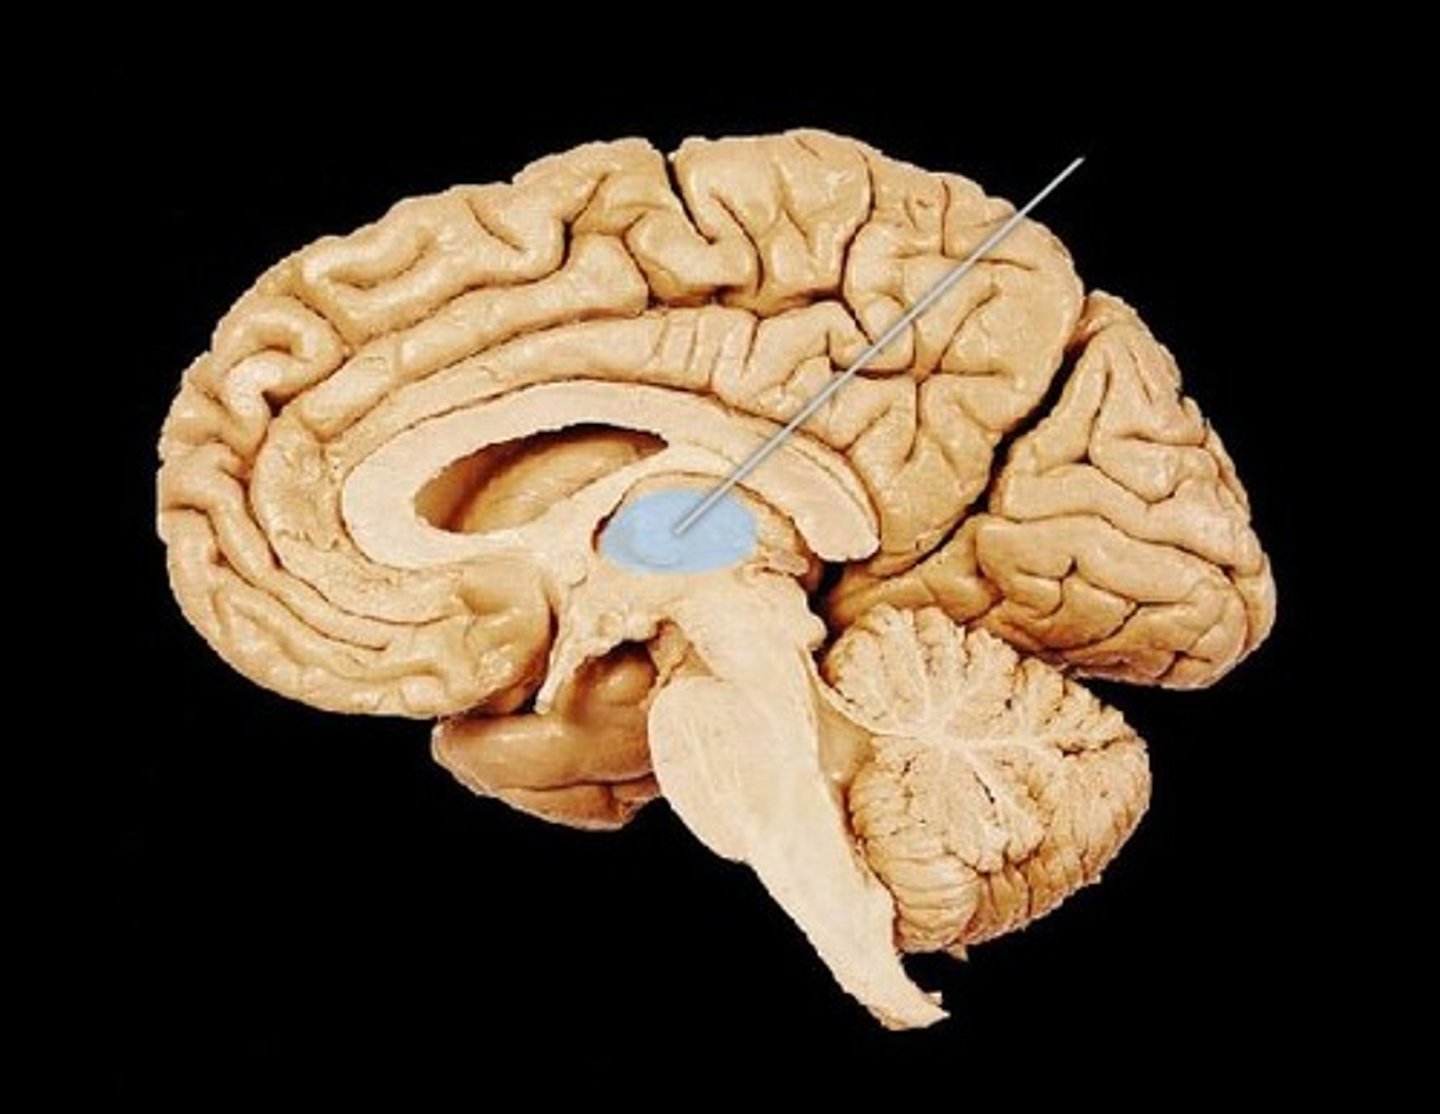

Hippocampus

small structure with two arms that wrap around the thalamus (blue in picture) - storage for conscious memories

Think of it like you have to remember how to get around a new campus